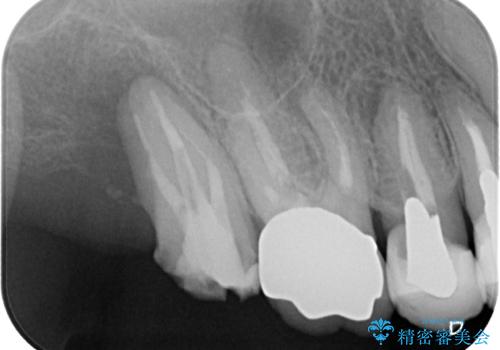

遠心が歯根破折しており、歯槽骨が著しく吸収している状態であったため、抜歯即時でのインプラント埋入は断念し、2ヶ月ほど待機してから埋入することとしました。

抜歯後2ヶ月でのインプラント埋入を行いましたが、骨の再生は不十分でした。

骨量は不十分でしたが、デンサーバーを用いることで無事に埋入することができ、その後は速やかに補綴治療を行うことができました。